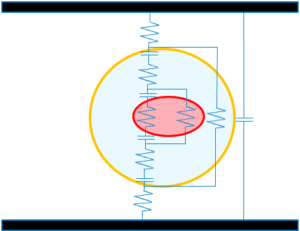

Quasi tutti i processi fisiologici sono basati su un valore di differenza di potenziale elettrico tra le due pareti cellulari e tra i vari tessuti.

TUTTO DIPENDE DALL’EQUILIBRIO BIOELETTRICO DELLA CELLULA

La cellula funziona come un condensatore che accumula e consuma energia mantenendola ad un valore di -70 mV.

Quando è scompensata per effetto patologico modifica il suo valore e di conseguenza non produce abbastanza ATP e la membrana è sottoposta ad uno stress

Un campo elettrico e una corrente simile a quella che si crea naturalmente (microcorrente), è in grado di modulare molti tra questi fattori che intervengono nella rigenerazione tissutale.

Viene così influenzata la migrazione di ioni attraverso la membrana cellulare con conseguente modifica del Citoscheletro inclusa la proiezione di membrane che provocano notevoli movimenti cellulari.